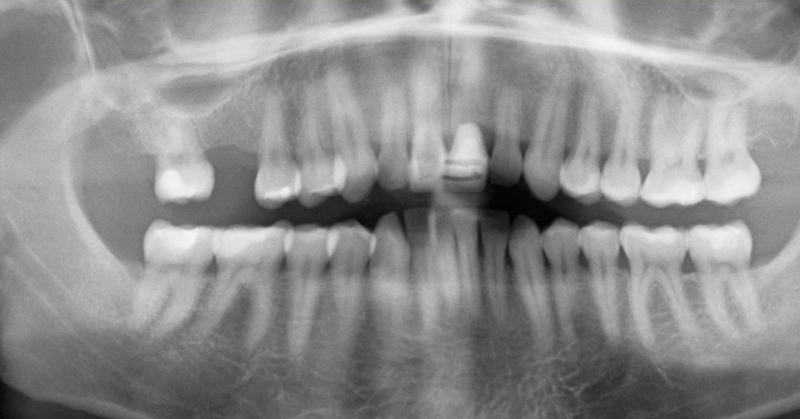

Old  Default Hãy cẩn thận: Khoang miệng có thể giết chết bạn!?!

Bạn có biết những gì thực sự đang xảy ra trong miệng của bạn?

Hiện nay, ngày càng có nhiều người đang tìm đến nha sĩ để giúp điều trị các vấn đề về răng như là một kết quả của một chế độ ăn uống và lối sống thiếu khoa học. Sự kết hợp không lành mạnh này chuyển thành một số điều kiện khác nhau mà có thể có ảnh hưởng lâu dài đến sức khỏe tổng thể của bạn.

Phần đáng sợ là không có nhiều người nhận thức được làm thế nào những vấn đề này có thể tác động tới sức khỏe của mình. Ví dụ, bạn có biết rằng các bệnh tự miễn dịch, rối loạn thần kinh, cũng như các bệnh mãn tính và cấp tính có thể xảy ra do ngộ độc thủy ngân trong trám amalgam?

Đồng thời, có những vấn đề khác có thể phát sinh từ nhiễm trùng mà đến như là một kết quả của ống tủy hoặc nhổ răng - về cơ bản, một khi bạn đi đến nha sĩ, điều đó không nhất thiết có nghĩa là nó là kết thúc của câu chuyện.

Răng của bạn là cơ quan riêng biệt.

Mỗi răng của bạn được liên kết với các cơ quan khác, các tuyến, và các mô mà biến cơ thể của bạn thành một mạng lưới các hệ thống hoạt động. Vì vậy, khi bạn đối phó với những vấn đề bên trong miệng của bạn, họ có thể lây lan đến các bộ phận khác của cơ thể của bạn nhanh chóng. Điều này có thể có một tác động có hại đến sức khỏe của hệ thống miễn dịch của bạn, và kết quả là một cơn lũ độc tố góp phần vào sự suy thoái của các mô và cơ quan của bạn.

Trong khi các vấn đề của răng đã rất nghiêm trọng, những vấn đề về răng có thể lây lan và tiếp tục lây nhiễm sang các bộ phận khác của cơ thể của bạn nhanh chóng. Đó là lý do tại sao điều quan trọng là phải chăm sóc chúng trong những cách lành mạnh nhất và nhanh nhất có thể, để giảm thiểu thiệt hại và đảm bảo rằng miệng của bạn vẫn khỏe mạnh trong một thời gian dài.